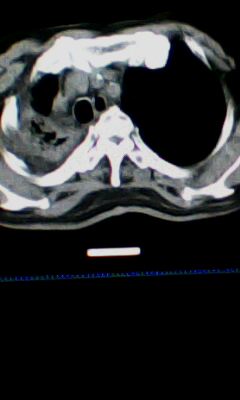

标题: CT25675:男 71 肺癌部分切除术后 3年 [打印本页]

标题: CT25675:男 71 肺癌部分切除术后 3年

两肺感染性病变,右侧肺膨胀不全,左侧上叶结节影及左侧颈部淋巴结肿大建议复查。

1)两肺感染性病变。2)右侧胸膜增厚。3)冠状动脉及主动脉钙化。

右肺炎症,左肺炎症。

右侧胸膜肥厚。

两肺感染性病变\\右侧胸膜增厚

1.右肺符合肿瘤切除术后ct表现。

术后改变,双肺内纤维索条影考虑与放疗有关。